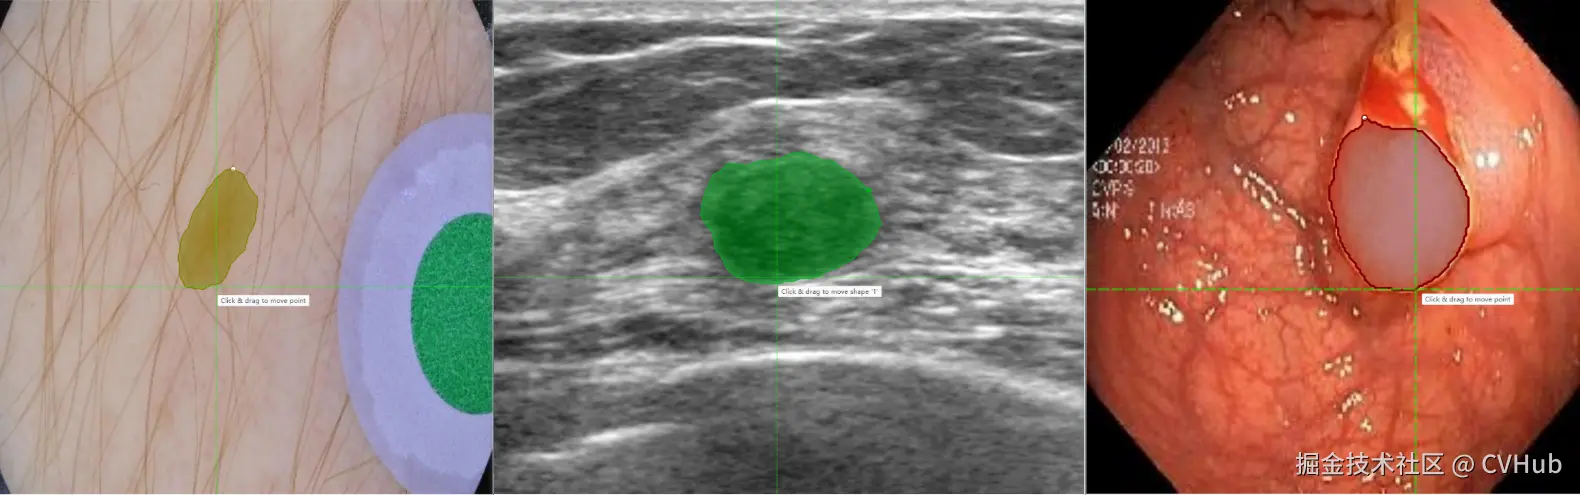

更进一步地,针对医学图像场景,X-AnyLabeling中同样提供了多种基于 SAM 微调的高精度模型,包括:

• SAM-Med2D: 通用医疗图像分割一切模型;

• LVM-Med ISIC SAM:皮肤病灶分割一切模型;

• LVM-Med BUID SAM:超声乳腺癌分割一切模型;

• LVM-Med Kvasir SAM:结直肠息肉分割一切模型;

详情可参考以下链接:

github.com/CVHub520/X-…